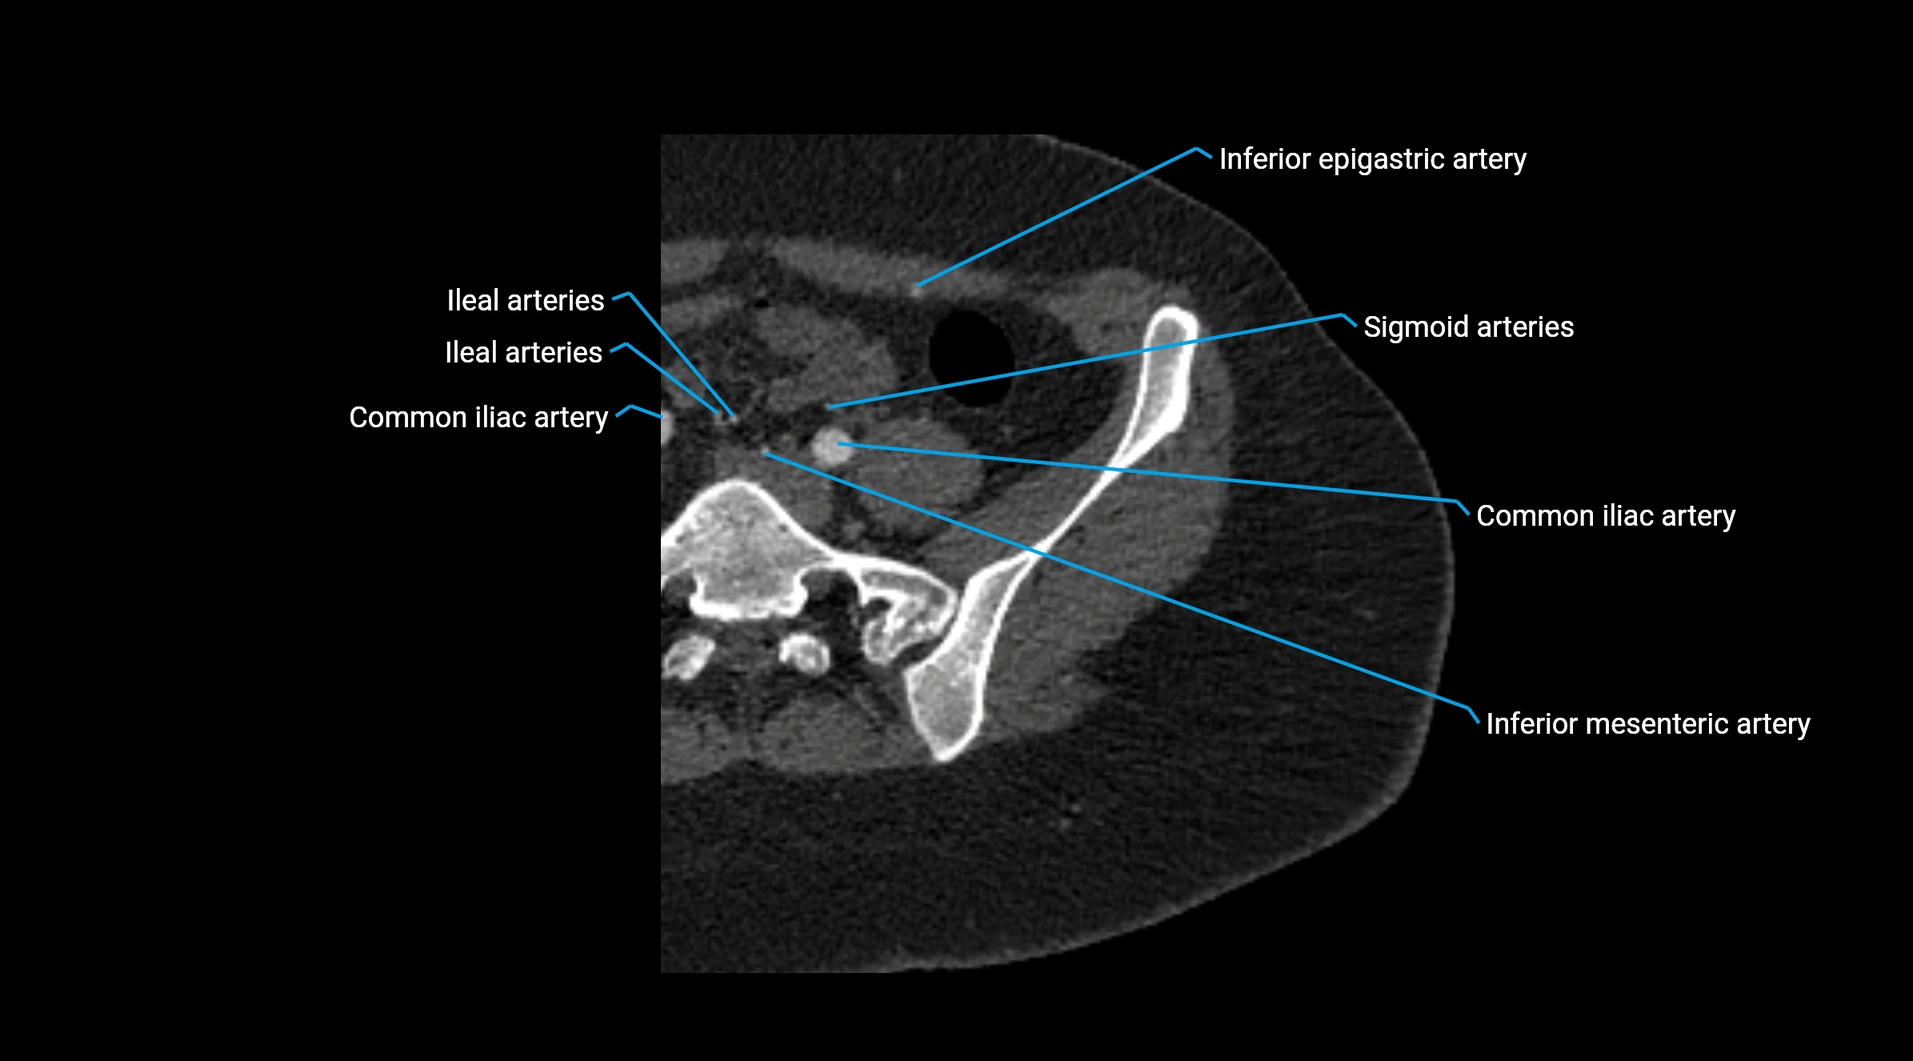

Contrast-enhanced CT (CTA):

• Gold standard for abdominal aortic imaging

• Provides excellent detail of lumen, wall, aneurysm, thrombus, and branch vessels

• Multiplanar and 3D reconstructions help in aneurysm measurement, stent graft planning, and dissection evaluation

• Detects acute rupture, traumatic injury, or occlusion with high sensitivity